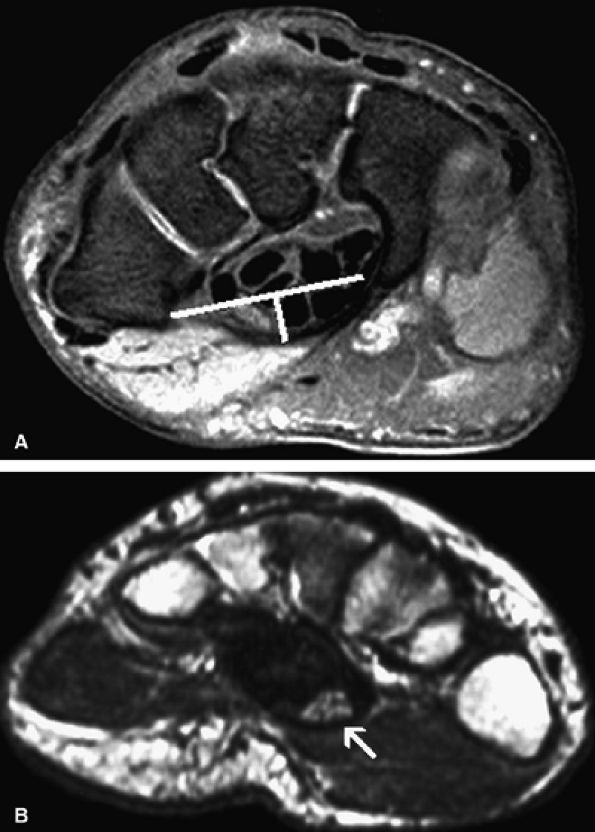

Size of the nerve. The cross-sectional area of the median nerve is significantly larger in patients with carpal tunnel syndrome than in asymptomatic individuals.116 However, the cutoff size of the cross-sectional area between a normal and a pathologic median nerve is unclear. To evaluate proximal enlargement of the median nerve on axial MR images, comparison of the cross-sectional area of the nerve at the level of the radioulnar joint and at the level of the pisiform bone should be obtained. In patients with carpal tunnel syndrome, the median nerve at the level of the pisiform may be twice or three times as large as at the level of the radioulnar joint.117

Nerve flattening. Flattening of the nerve can be evaluated using flattening ratios, defined as the ratio between the major and minor axes of the nerve both at the level of the distal radioulnar joint and at the level of the hook of the hamate.117 A flattening ratio greater than 3 at the level of the hook of the hamate may indicate median nerve pathology.

Flexor retinaculum bowing. Bowing of the flexor retinaculum likely reflects increased pressure or volume within the carpal tunnel. In normal individuals, the flexor retinaculum at the level of the hook of the hamate should be flat or slightly convex. The degree of bowing is determined by dividing the distance of palmar displacement of the retinaculum by the distance between the hook of the hamate and the tubercle of the trapezium. In normal patients, the ratio varies from 0 to 0.15 (mean 0.05). In carpal tunnel syndrome, however, the ratio varies from 0.14 to 0.26 (mean 0.18).117

![]() |

FIGURE 12.45 ● Carpal tunnel syndrome. (A) Axial fat-suppressed T2-weighted image through the distal carpal tunnel demonstrates enlargement of the median nerve with bowing of the flexor retinaculum. The bowing ratio of the flexor retinaculum, determined by dividing its palmar displacement by the distance between the hook of the hamate to the tubercle of the trapezium, was 0.18 (normal ratio, 0 to 0.15). (B) Axial T2-weighted image through the proximal metacarpal region shows a swollen and hyperintense median nerve (arrow).